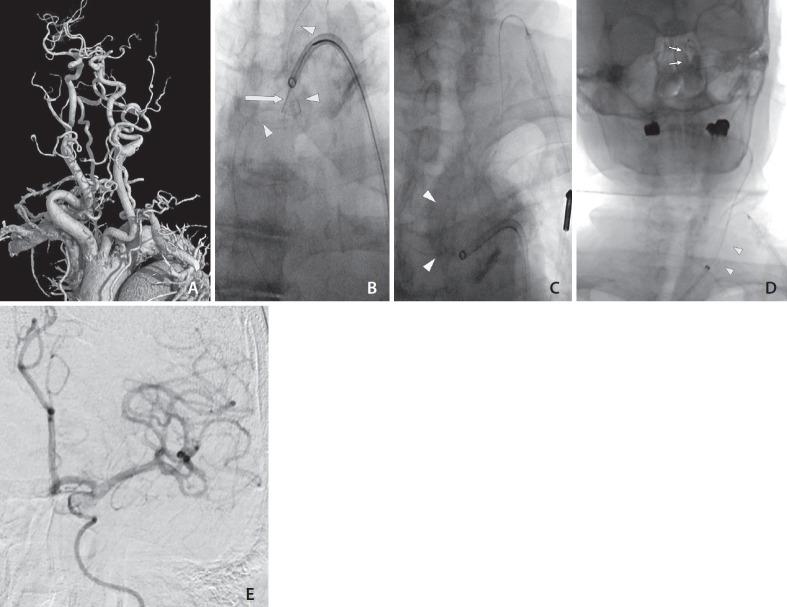

Excessive tortuosity is a notable cause of failed endovascular thrombectomy for acute large-vessel occlusion stroke. Transcervical access (TCA) is a commonly proposed solution for overcoming this difficulty. However, the large-bore catheter usually used in TCA increases the risk of serious local complications. This paper presents a modified technique for TCA that uses a pull-through buddy wire (PTBW) to track a large-bore femoral guiding sheath (GS) into the carotid artery via a small carotid puncture site. The carotid puncture site can be easily managed through gentle manual compression. Two illustrative cases using this technique to deal with a large aortic arch and tortuous left common carotid artery are reported. In both cases, recanalization was achieved after successful GS placement. Using a PTBW is feasible in TCA.

过度迂曲是急性大血管闭塞性卒中血管内血栓切除术失败的一个显著原因。经颈入路(TCA)是克服这一困难常用的解决方案。然而,TCA中通常使用的大口径导管会增加严重局部并发症的风险。本文介绍了一种改良的TCA技术,该技术使用牵引导丝(PTBW)通过小的颈动脉穿刺点将大口径股动脉引导鞘(GS)送入颈动脉。通过轻柔的手动压迫可以轻松处理颈动脉穿刺点。报告了两例使用该技术处理大主动脉弓和迂曲的左颈总动脉的病例。在这两例中,成功放置GS后均实现了再通。在TCA中使用PTBW是可行的。